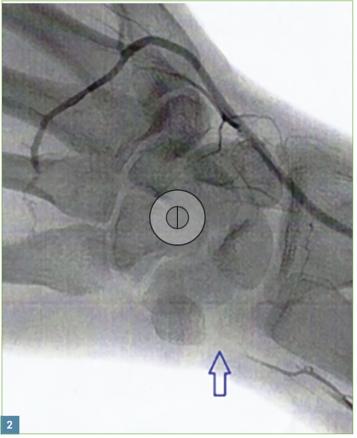

Pour confirmer le diagnostic, un doppler est réalisé. L’artériographie objective une obstruction de l’artère ulnaire (fig. 2 ; flèche).

Pour confirmer le diagnostic, un doppler est réalisé. L’artériographie objective une obstruction de l’artère ulnaire (